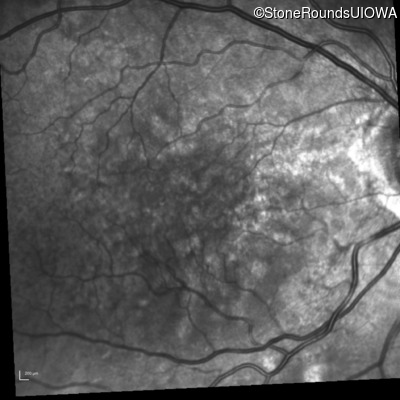

Infrared Fundus Photograph - Right - 20/40

Exemplar